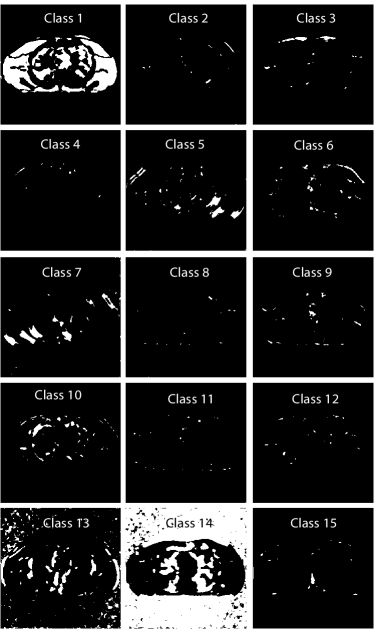

V-A2 Behavior of the learned ULTRA Models

The learned union of transforms contributes to the clustering and sparsification of image patches. To illustrate the behavior of the learned transforms, we selected 3 of the 15 transforms that capture important structures/features of the reconstructed image (with I0=1×104subscript𝐼01superscript104I_{0}=1\times 10^{4}) in their classes.

Refer to caption

Figure 2: The three rows correspond to the 1st, 13th, and 14th classes respectively. The first column displays three voxel-level clustered images of the central axial slice. Each of them is formed by image patches lie in the corresponding class. The second column displays part of the transforms for the corresponding classes. The third, fourth and fifth columns show the central axial slice of the sparse coefficient maps obtained by applying specific filters (shown in the top left corner) to patches belonging to the corresponding classes. The patch stride for plotting these figures was 1×1×11111\times 1\times 1.

Fig. 2 (first column) shows three voxel-level classes (voxels are clustered by majority vote among patches overlapping them) for the reconstructed central axial slice. The top image only contains soft tissues, whereas the middle image shows some edges and bones in the vertical direction, and the bottom image captures some high-contrast structures. Fig. 2 (second column) shows the transforms for the corresponding classes. Each learned transform has 512 8×8×88888\times 8\times 8 filters, and we show the first 8×8888\times 8 slice of 256 of these filters that show gradient-like and directional features.

Fig. 2 also shows the central axial slice of the sparse coefficient maps (volumes) for different filters of the transforms in the third, fourth and fifth columns. Each voxel value in a sparse coefficient map is obtained by applying the specific 3D filter to a 3D patch (whose front top left corner is at that voxel) and hard-thresholding the result. Coefficients for patches not belonging to the specific class are set to zero (masked out). The sparse code maps capture different types of image features (e.g., edges at different orientations or contrasts) depending on the filters and classes.